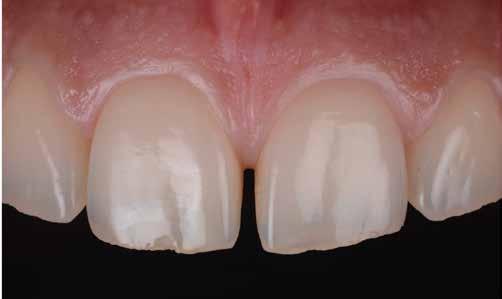

ezen a területen, a fogászat profitál az ilyen fejlesztésekből, és ma már számos kezelési megoldást kínálunk pácienseinknek. Rezidens korom alatt klinikai szakfelügyelőként dolgoztam akadémiai környezetben, ahol elsősorban kivehető fogpótlásra szoruló geriátriai betegeket kezeltem, valamint olyanokat, akiknek fix fogpótlásra, például fog- vagy implantátummal ellátott hagyományos rögzített fogpótlásra (azaz korona és híd) volt szükségük, elsősorban arany vagy fémkerámia felhasználásával. Az ezekben az években megfigyelt klinikai kudarcok és a beavatkozások invazív jellege, nevezetesen a foghúzásra vonatkozó több fúrás és egyszerűbb döntések jelentős szerepet játszottak a kutatási irányvonalam kialakításában az évek során. Ez volt az az időszak is, amikor elkezdtem többet foglalkozni az adhezív fogászattal, ami megváltoztatta a protetikai fogászat klasszikus arculatát, és határozottan kevésbé invazívvá tette azt (1. a-d ábrák). Ma, az intenzív transzlációs és klinikai kutatás eredményeként, különös tekintettel a fogászati bioanyagok alkalmazására, klinikai szakértelmem a minimálisan invazív, adhezív eljárások alkalmazására összpontosít a protetikai fogászatban, a szövődmények kezelésére és a költséghatékony kezelési lehetőségek felkínálására.

1. a-d ábrák: a) Fogerózió a molárisok okkluzális felszínén, b) maratás foszforsavval, c) minimálisan invazív műgyanta-kompozit fedőréteg levegővel történő felszívása, d) adhezív ragasztott fedőréteg a hiányzó zománc és dentin helyreállítására.